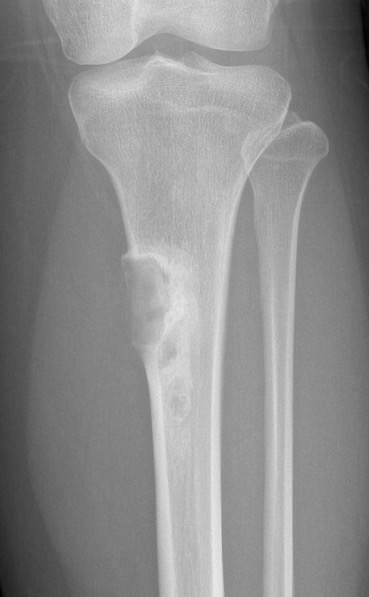

Adamantinoma

Biopsy proven adamantinoma

X-ray

Most common anterior cortex of tibia

Soap-bubble appearance

Eccentrically located

- well circumscribed

- slightly expansile

- cortical thickening

- little or no periosteal reaction